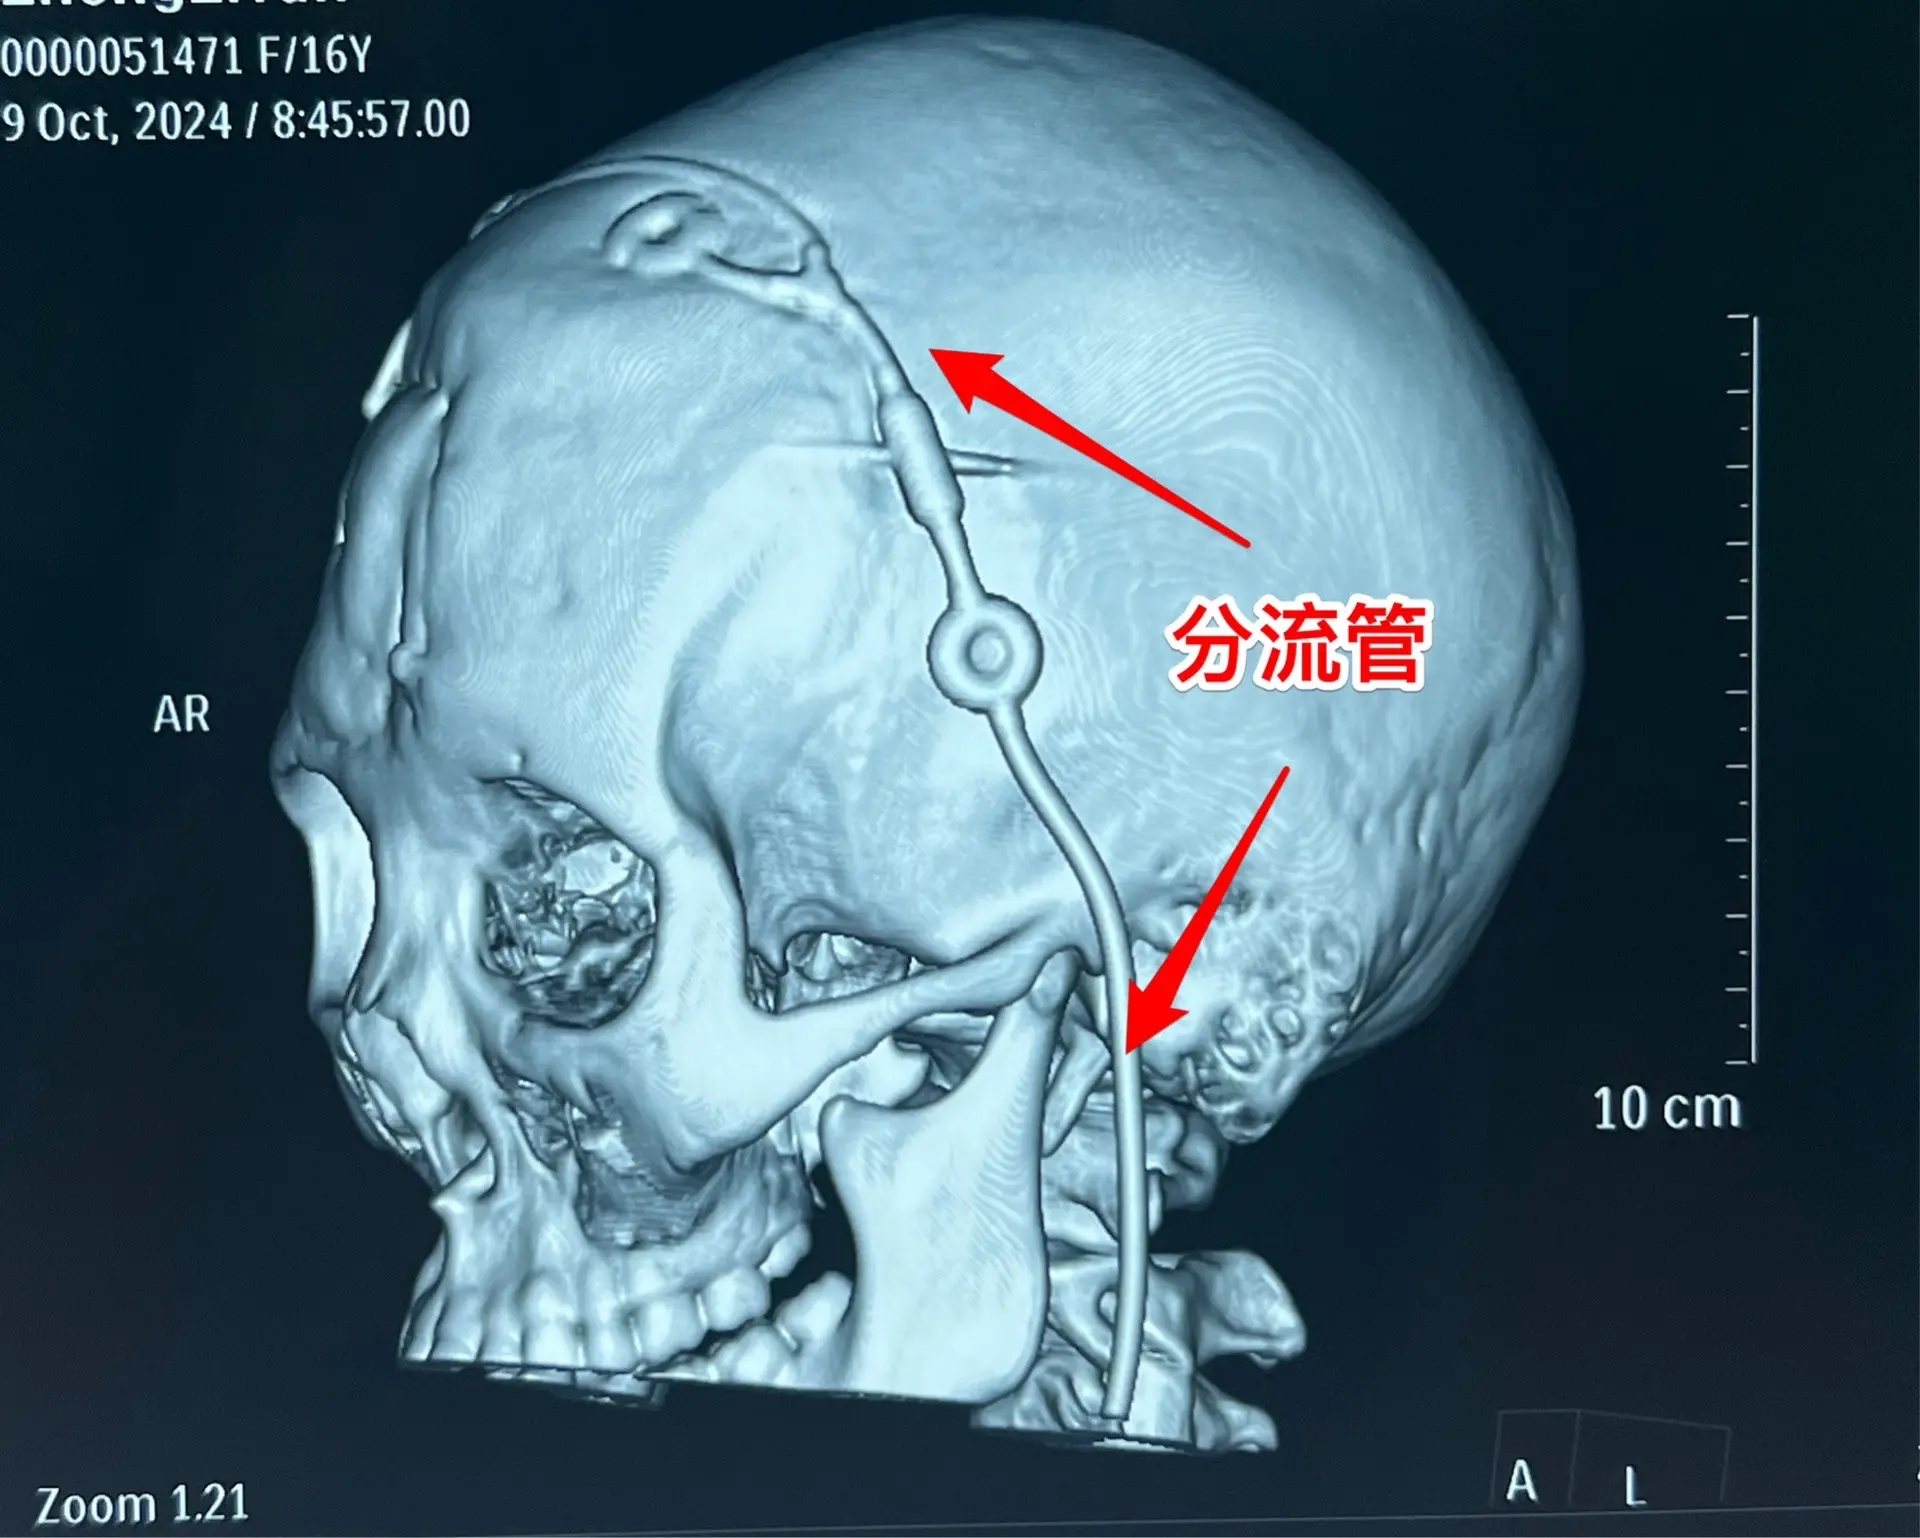

3次复发的颅咽管瘤也要积极治疗。16岁杭州女生,因颅咽管瘤于10年前在外院行开颅手术。8年前发现颅咽管瘤复发(在右侧额叶-鞍区)在我科作了手术,随后多年复查磁共振,7年内均未见肿瘤复发。本以为她的颅咽管瘤已经得到治愈,不曾想八个月前行磁共振检查发现肿瘤有复发迹象,体积很小,观察八个月常规复查磁共振发现肿瘤体积增大了许多,见图,肿瘤起源于左侧桥脑-中脑表面,和普通的颅咽管瘤位置不同。 10月11日作了手术,将这个复发肿瘤彻底切除了。手术后女孩子恢复很顺利,希望经过三次手术后肿瘤不再复发。